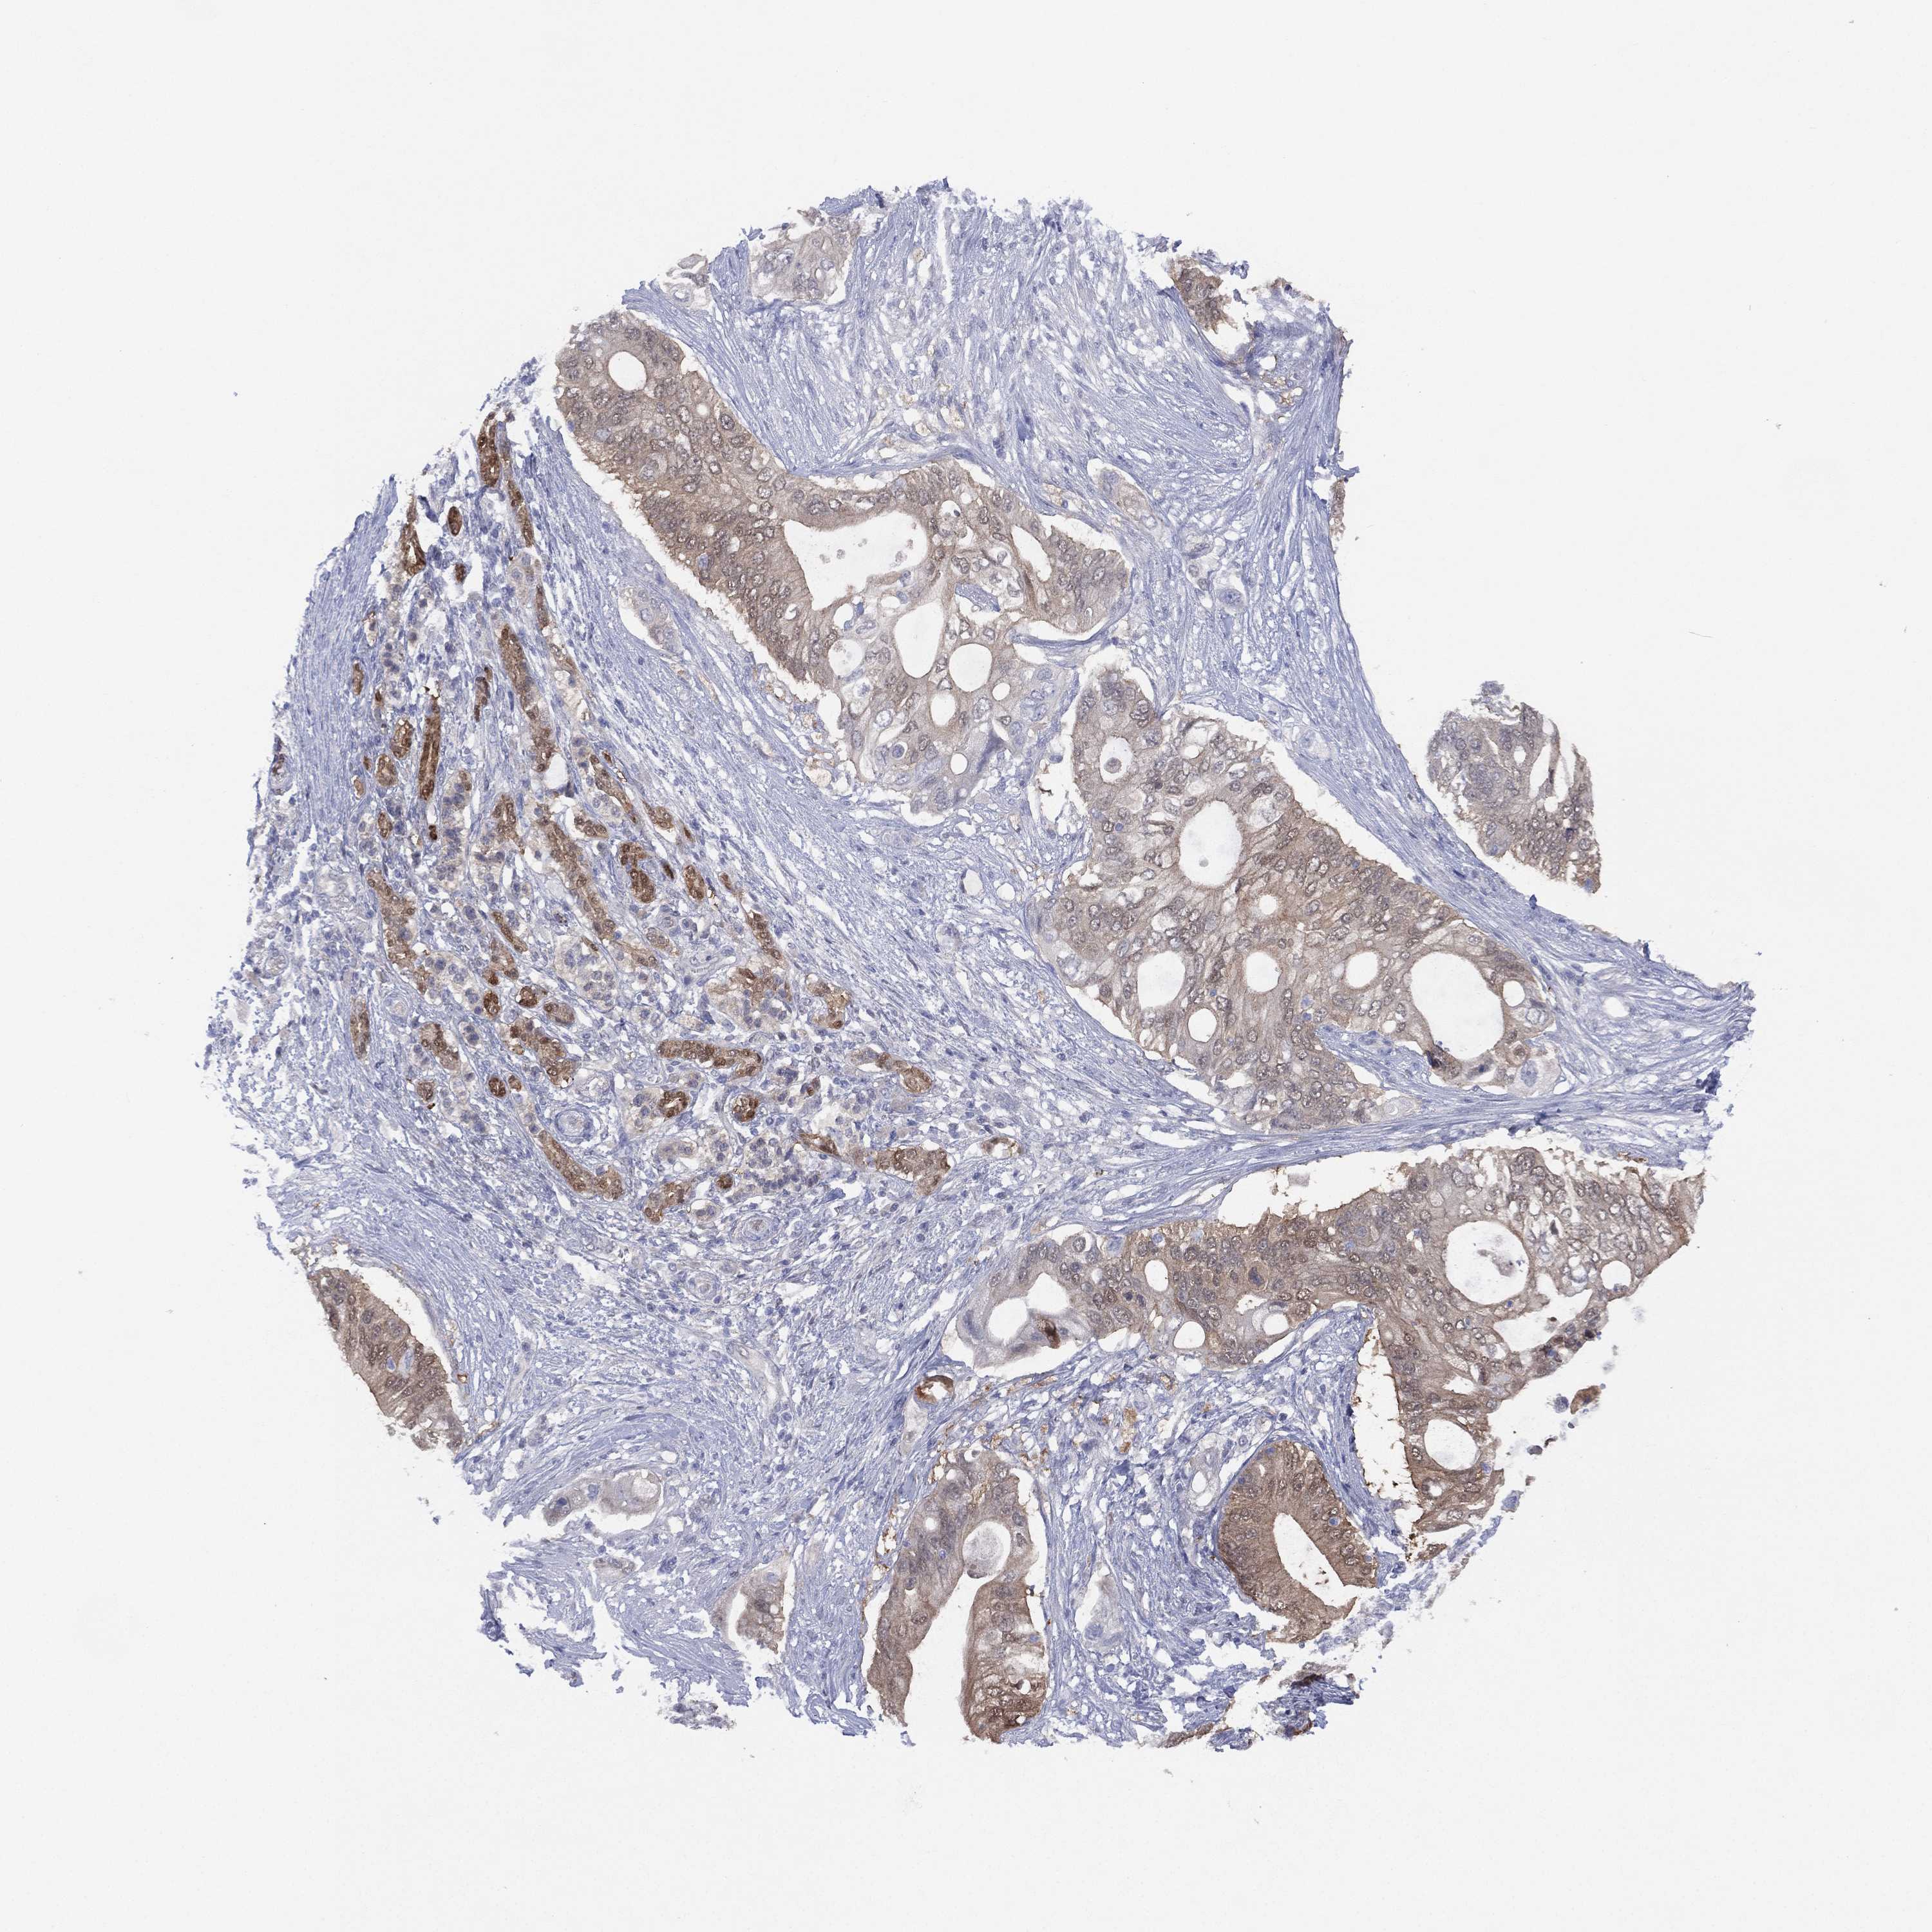

PANCREATIC CANCER - Protein expressioni

A mouse-over function shows sample information and annotation data. Click on an image to view it in a full screen mode. Samples can be filtered based on level of antibody staining by selecting one or several of the following categories: high, medium, low and not detected. The assay and annotation is described here.

Note that samples used for immunohistochemistry by the Human Protein Atlas do not correspond to samples in the TCGA dataset.

Antibody stainingi

Antibody staining in the annotated cell types in the current human tissue is reported as not detected, low, medium, or high, based on conventional immunohistochemistry profiling in selected tissues. This score is based on the combination of the staining intensity and fraction of stained cells.

Each image is clickable and will lead to virtual microscopy that enables deeper exploration of all samples and also displays staining intensity scores, fraction scores and subcellular localization as well as patient and tissue information for each sample.

Antibody HPA006308

Antibody HPA071064

Staining

High

Medium

Low

Not detected

Intensity

Strong

Moderate

Weak

Negative

Quantity

>75%

75%-25%

<25%

None

Location

Nuclear

Cytoplasmic/membranous

Cytoplasmic/membranous,nuclear

Adenocarcinoma, NOS

Adenocarcinoma, metastatic, NOS